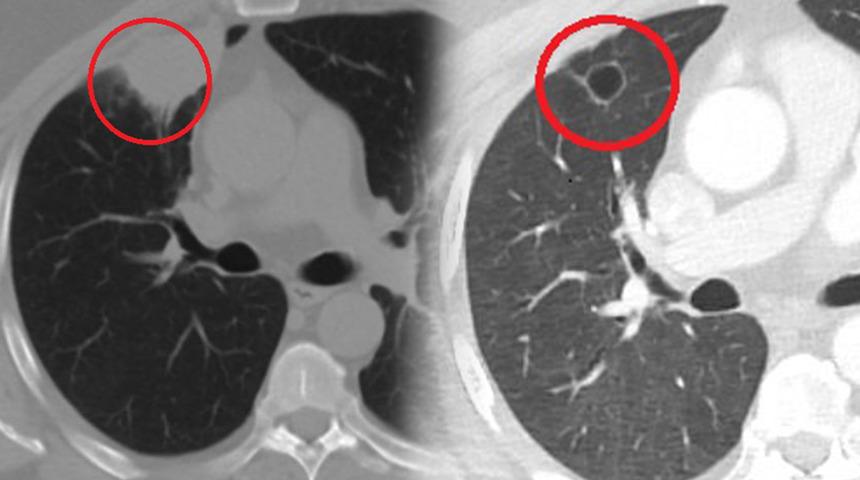

Kent dışında çalışan N.T.'nin, göğüs ağrısı şikayetiyle gittiği hastanede çekilen tomografisinde sağ akciğerinde 4 santimetre çapında tümör tespit edildi. Kanser olabileceği şüphesiyle yapılan ileri tetkikler sonrası N. T.'ye akciğer kanseri teşhisi kondu ve acil ameliyat kararı verildi. Bunun üzerine N.T., ameliyat için memleketi Kahramanmaraş'a geldi. Sütçü İmam Üniversitesi Sağlık Uygulama ve Araştırma Hastanesi Göğüs Cerrahi Anabilim Dalı Öğretim Üyesi Dr. Fatoş Kozanlı da tomografi ve test sonuçlarına göre N. T.'ye akciğer kanseri teşhisi koydu ve ameliyat yapılması gerektiğini söyledi.

Ameliyat öncesi N.T.'nin koronavirüs testi pozitif çıkınca operasyon ertelendi. Koronavirüs tedavisine başlanan N.T.'nin son testi negatif çıktı. Dr. Fatoş Kozanlı, tedavi sonrası tomografisi çekilen N.T.'nin akciğerindeki tümörün yok olduğunu gördü. Kozanlı, N.T.'nin kendilerine başvurduğunda koronavirüs belirtisi olmadığını ancak ameliyat öncesi PCR testi yaptıklarını söyledi. Koronavirüs tedavisinin ardından ortaya çıkan sonucun kendisini de şaşırttığını belirten Kozanlı, şunları söyledi:

"Hastamız, çalıştığı başka bir kentte göğsünden darbe alıyor ve ağrıları geçmeyince bir üniversite hastanesine başvuruyor. Burada hastaya bir akciğer grafisi çekiliyor. Sağ akciğerinde bir kitleye rastlanıyor. Daha sonra hastaya, bir akciğer tomografisi çekiliyor ve göğüs cerrahisi için önemli büyüklükte olan 4 santimetre çapında, akciğer kanserine benzer özellikte radyolojik bulgular olan bir kitle tespit ediliyor. Daha sonra hastaya yapılan ileri tetkiklerde akciğer kanseri teşhisi konuluyor. Hastaya bir cerrahi planlanıyor. Hasta Kahramanmaraşlı olduğu için kendi memleketine gelmeyi tercih ediyor. Bize başvurdu ve göğüs ağrısı şikayeti vardı. Öksürük, nefes darlığı, balgam çıkarma, ateş gibi şikayetleri yoktu. Hastayı biz de değerlendirdik ve ameliyat olmasına karar verdik. Çünkü akciğer kanserine çok benzer radyolojik bulguları vardı. Sağlık Bakanlığımızın kuralları gereği her hastayı ameliyat öncesi PCR testi yapılır. Biz de ameliyat gecesi hastadan PCR testi aldık ve testi pozitif geldi. Ameliyatımızı 14 gün erteledik ve hastamıza koronavirüs tedavisi uygulandı. Hasta 14'üncü gün tekrar bize başvurdu ve yapılan PCR testi negatif çıktı. Yeni bir tomografi çektik ve tümörün tamamen ortadan kalktığını gördük. Şimdi sonuç bilgilerinden başlangıca gittiğimizde, bu bir akciğer kanseri olsaydı, ortadan kalkması mümkün değildi. Başka bir patolojiye bağlı durum olsaydı, yine verdiğimiz tedaviyle ortadan kalkmasını çok beklemeyiz. Antiviral tedavisi verdik ve hastanın radyolojik bulguları neredeyse tamamen normale döndü. Hastaya bunu izah ettik, 'Dünya literatüründe hiç görülmeyen bir radyolojik bulgu' diyerek. Bu gördüğümüz manzara artık hastanın akciğer grafisinde yok, akciğer kanseri değil. "